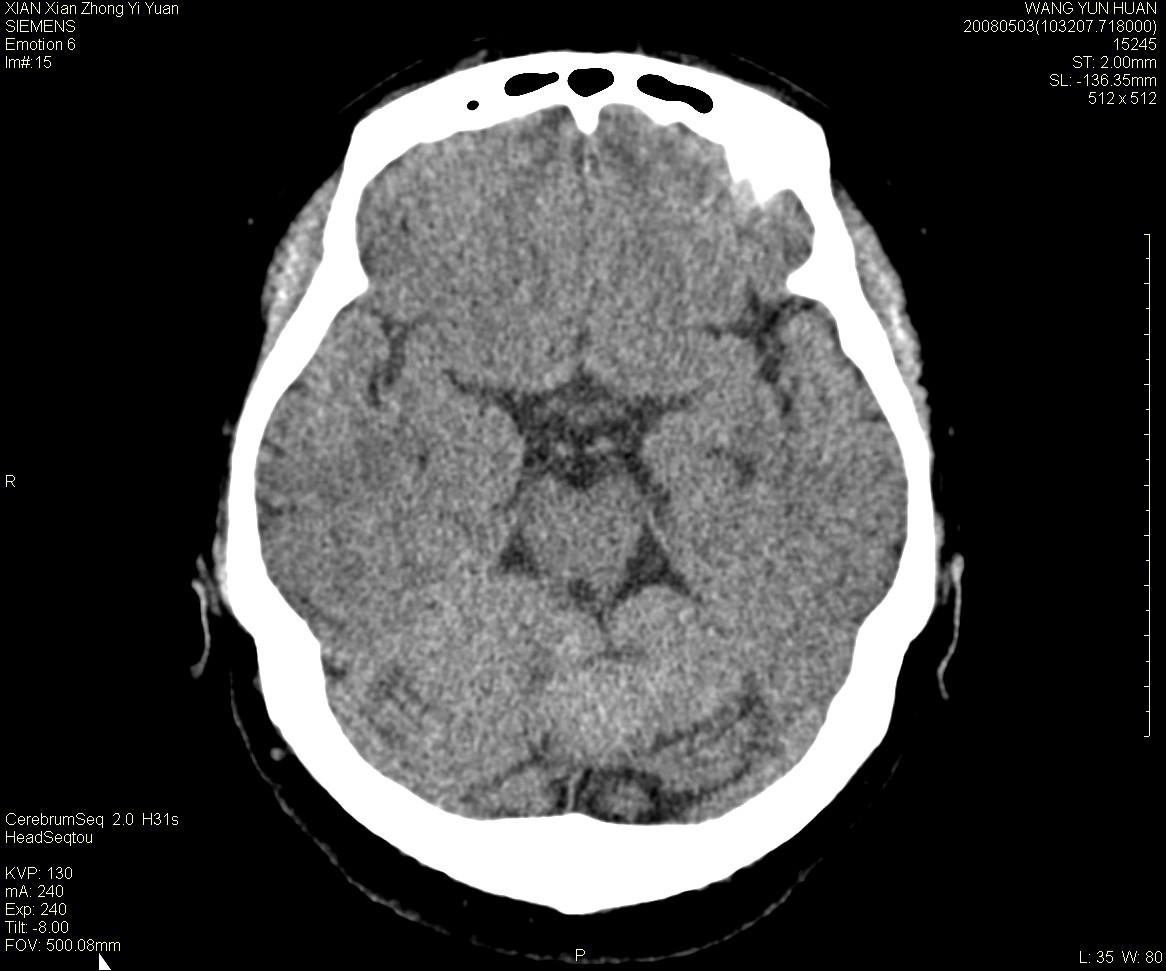

标题: CT13219:(补充强化)请会诊,患者女,60岁,头晕,大家看 [打印本页]

标题: CT13219:(补充强化)请会诊,患者女,60岁,头晕,大家看

病灶显示轻度强化,ct增加4hu左右,大家看是什么肿瘤.

小脑蚓部囊型肿块,内有实性结节及钙化点。增强后囊壁及结节轻度强化。

考虑蚓部星形细胞瘤(ⅱ级可能性大)。

小脑蚓部肿块,周围无明显占位效应及水肿带,增强轻度强化,考虑低分级星形细胞瘤。